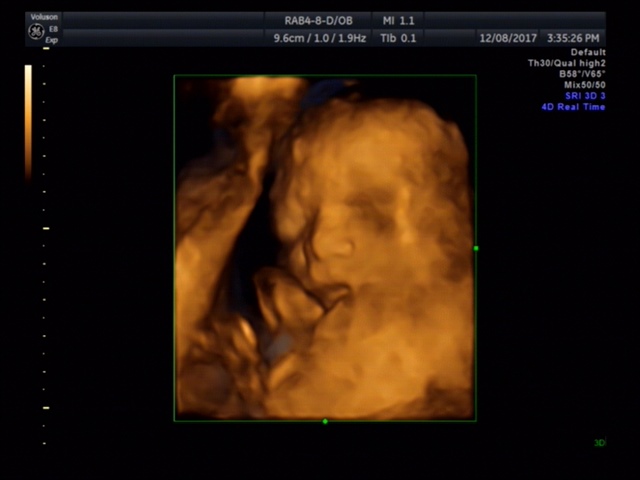

JESSICA👣

宝宝3个月12天

孕12周+4天

鼻子应该很高,好看^_^

JESSICA👣[帖主]:医生说鼻子很像我是个高鼻梁水滴鼻,嘴唇的轮廓也有点像,其他就不清楚了。